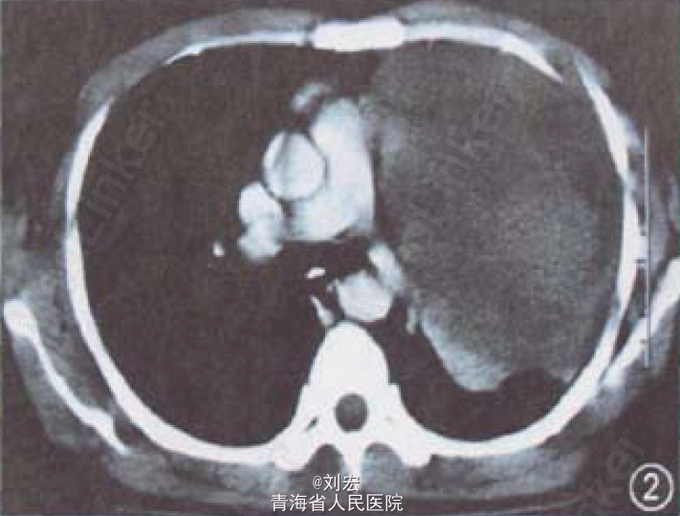

查体:左肺扣诊呈实音,呼吸音减弱。辅查:实验室检查未见明显异常;X线胸片可见左上肺巨大肿物(图1);胸部CT示左肺巨大肿物,内有数个点状钙化灶(图2);增强CT可见肿物轻度均匀强化。行CT引导下经皮肺穿刺活检,病理检查诊断为肺神经鞘瘤。

诊断:肺神经鞘瘤。处理:于外科行左肺肿瘤切除术,由于瘤体巨大,表面切开后吸出坏死组织后切除肿瘤。术后病理证实为来源于肋间神经的巨大神经鞘瘤。